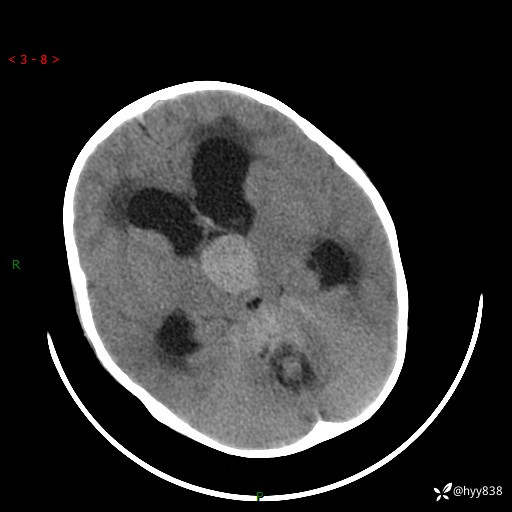

颅脑CT平扫

三脑室、四脑室多发病变,如何分析?